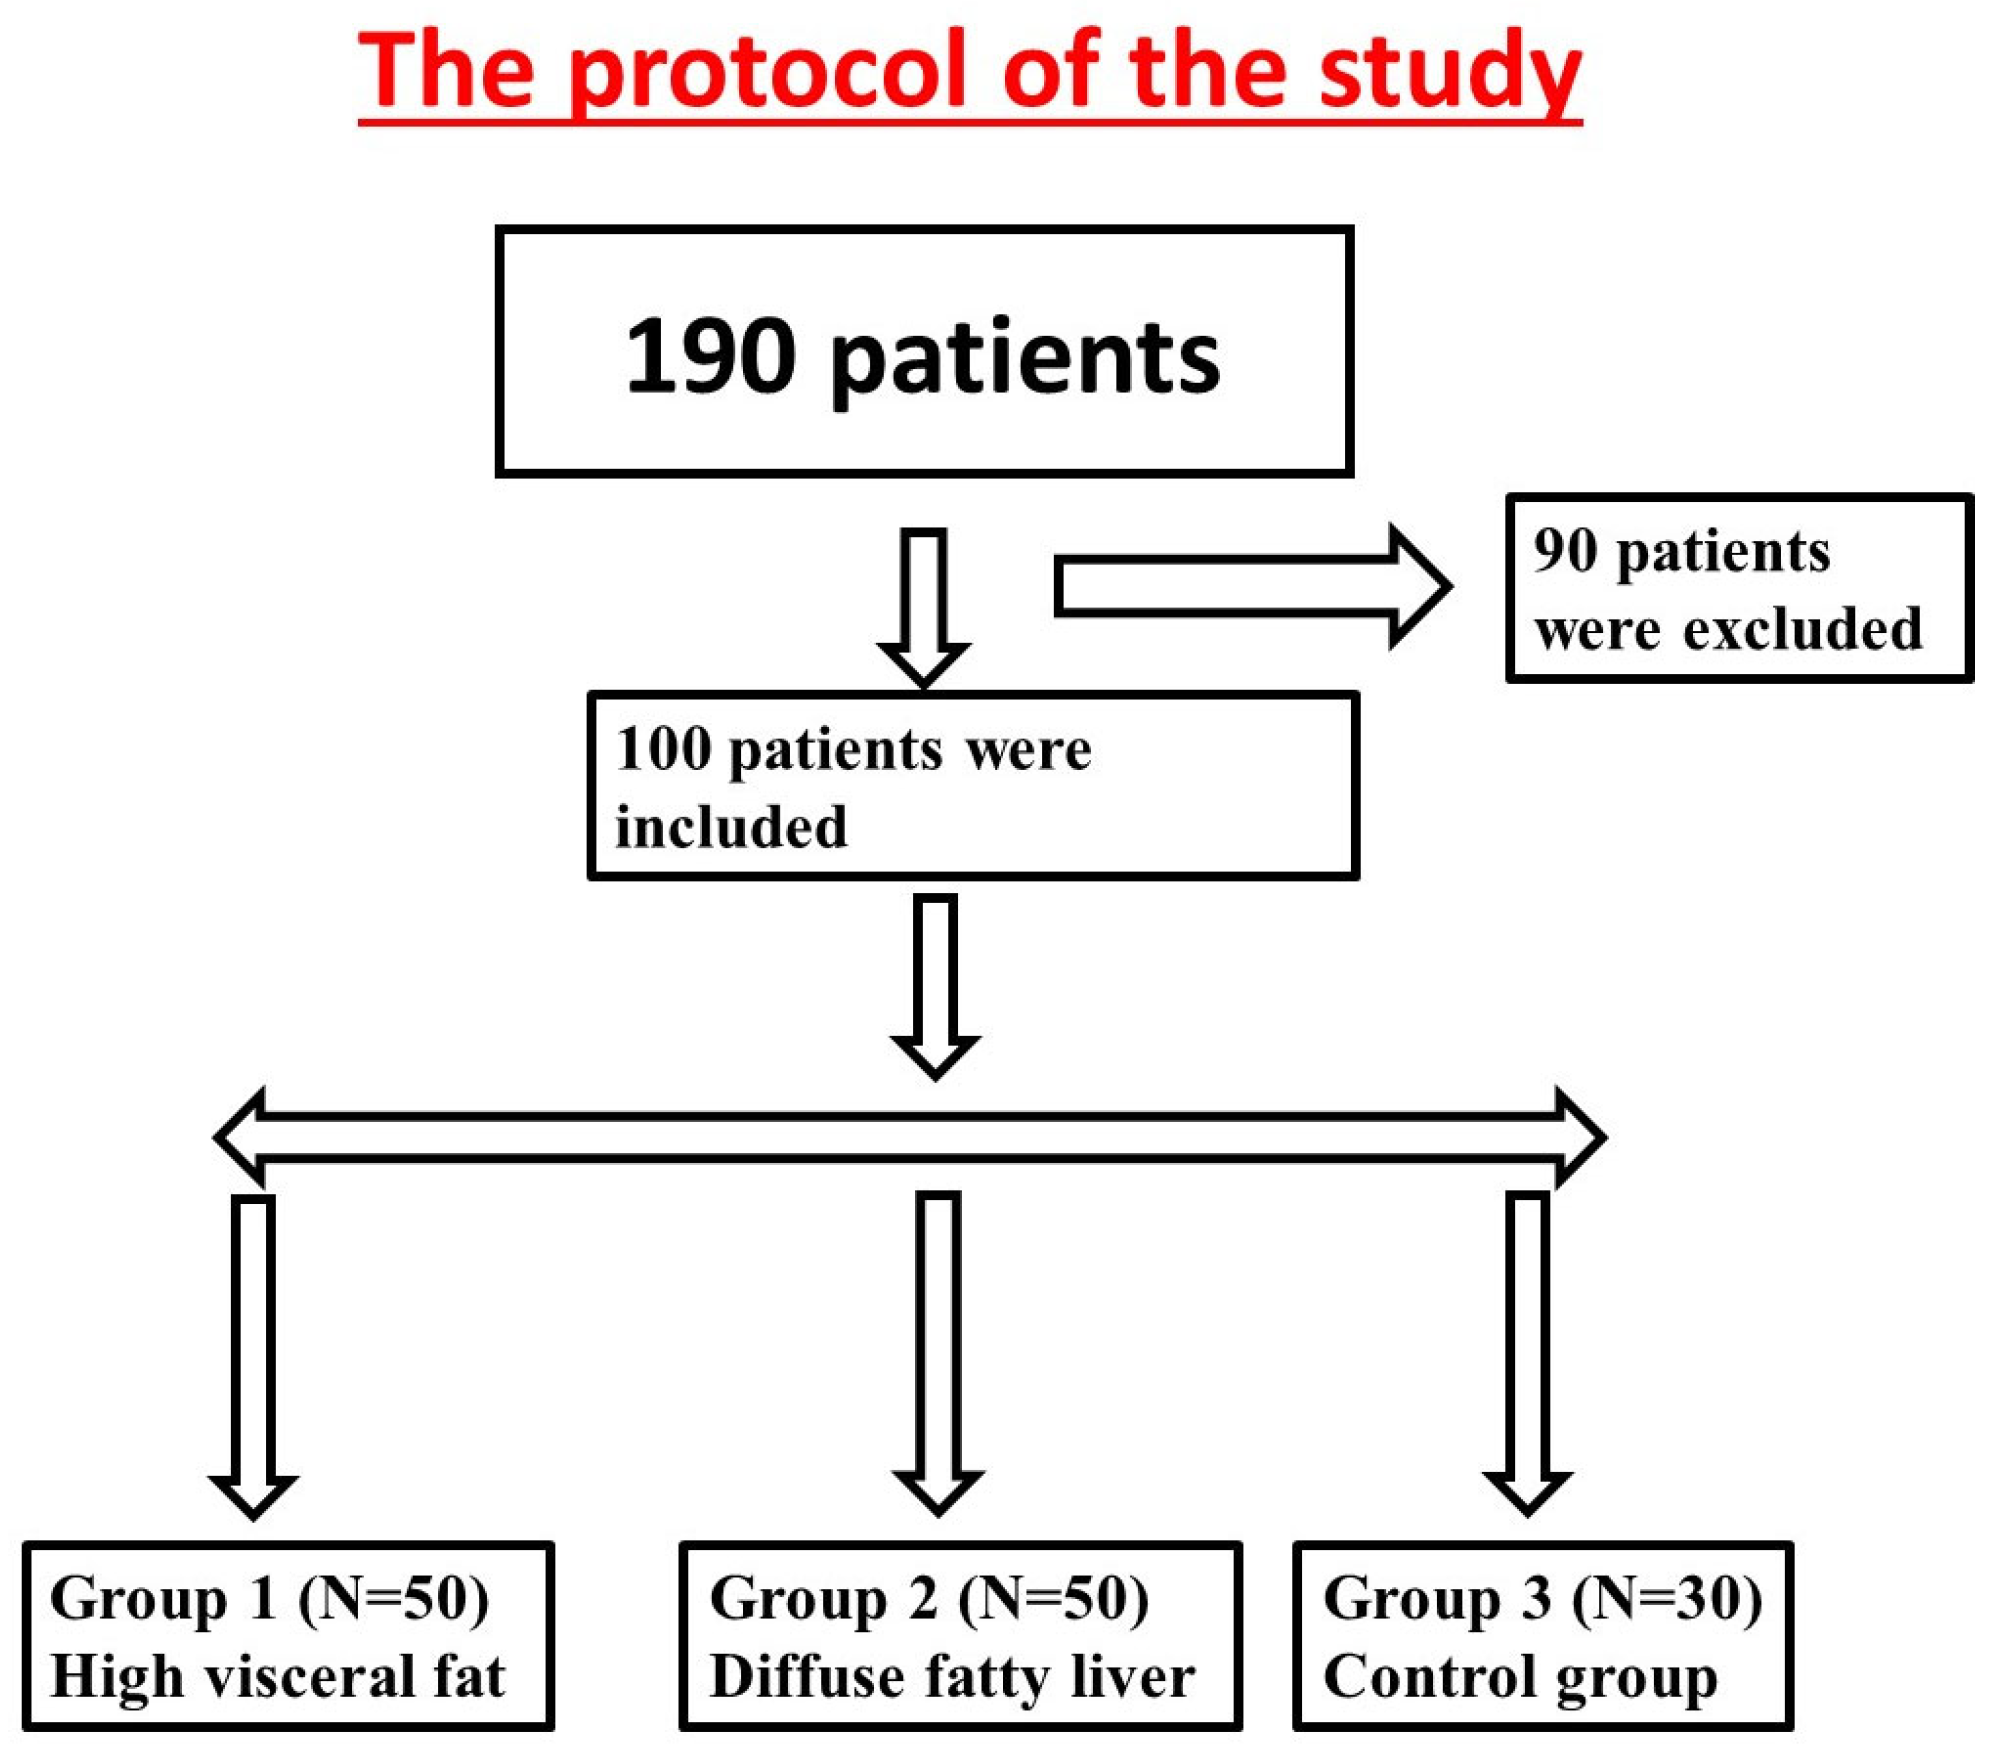

2. Materials and Methods

2.1. Study Population

2.2. Eligibility Criteria

2.2.1. Inclusion Criteria

2.2.2. Exclusion Criteria

2.3. Study Design